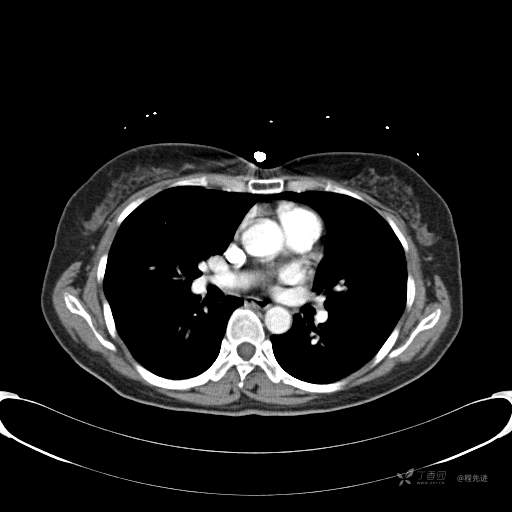

CT增强

平扫CT值约40HU(未上传图像),增强后动脉期CT值约70HU,静脉期CT值约97HU。